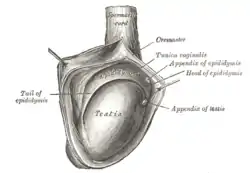

| The right testis, exposed by laying open the tunica vaginalis. (Tunica vaginalis is labeled at upper right.) | |

A hydrocele testis is an accumulation of clear fluid within the cavum vaginale, the potential space between the layers of the tunica vaginalis of the testicle. It is the most common form of hydrocele and is often referred to simply as a "hydrocele". A primary hydrocele testis causes a painless enlargement in the scrotum on the affected side and is thought to be due to the defective absorption of fluid secreted between the two layers of the tunica vaginalis (investing membrane). A secondary hydrocele is secondary to either inflammation or a neoplasm in the testis.

During embryogenesis, the testis descends through the inguinal canal, drawing a diverticulum of peritoneum into the scrotum as it descends. This peritoneal tissue is known as the processus vaginalis. Normally, the communication between the processus vaginalis and the peritoneum is obliterated, and the tunica vaginalis is the tissue that remains overlying the testis and the epididymis. Congenital hydrocele testis results when the processus vaginalis remains, allowing fluid from the peritoneum to accumulate in the scrotum.